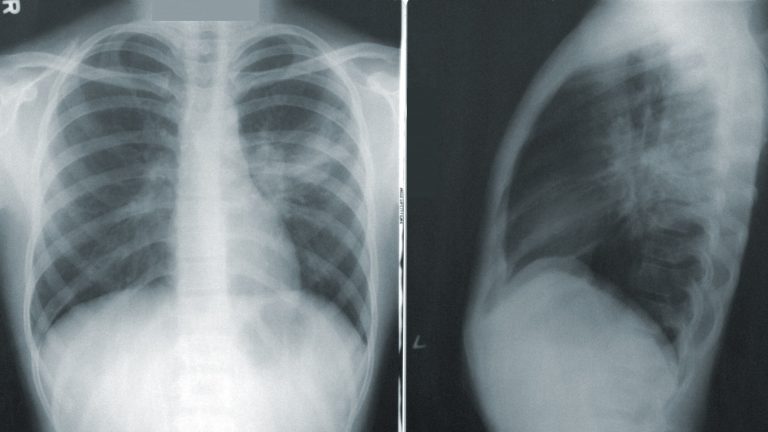

كوفيد-نِت هي عبارة عن شبكة عصبونية ملتفة، وهي نوع من الذكاء الاصطناعي تتميز بشكل خاص بجودتها في التعرف على الصور. وتم تطوير كوفيد-نِت من قِبل ليندا وانج وأليكساندر وونج في جامعة ووترلو وشركة داروين إيه آي الكندية المتخصصة بالذكاء الاصطناعي. وقد جرى تدريب كوفيد-نِت على تحديد علامات الإصابة بكوفيد-19 في صور الأشعة السينية للصدر باستخدام 5,941 صورة تم التقاطها لـ 2,839 مريضاً يعانون من أمراض رئوية مختلفة، بما فيها الالتهابات البكتيرية والتهابات فيروسية غير متعلقة بفيروس كوفيد-19، بالإضافة إلى حالات إصابة بكوفيد-19. وقد أتاح مطورا الشبكة الوصولَ إلى هذه البيانات بالإضافة إلى الأداة حتى يتمكن الباحثون -أو أي أحد يرغب في تجربتها- من استكشافها وتعديلها.

خلال الأسابيع القليلة الماضية، أعلنت العديد من الفرق البحثية عن تطوير أدوات ذكاء اصطناعي تستطيع تشخيص الإصابة بفيروس كوفيد-19 اعتماداً على صور الأشعة السينية. ولكن لم يتم توفير الوصول إلى أي منها أمام الجمهور، مما يجعل من الصعب تقييم دقة هذه الأدوات. بينما تتخذ داروين إيه آي مساراً مختلفاً؛ حيث تشير الشركة إلى أن كوفيد-نِت "ليست بأي حال من الأحوال حلاً جاهزاً للإنتاج"، وتشجع الشركة الآخرين على المساعدة في تطويرها وتحويلها إلى أداة جاهزة للاستخدام. كما أن داروين إيه آي -التي سيتحدث رئيسها التنفيذي شيلدون فيرنانديز اليوم [25 مارس] ضمن فعاليات مؤتمر إيمتيك ديجيتال- ترغب في أن تتمكن هذه الأداة من تفسير منطق عملها، مما يسهل استخدامها على العاملين في مجال الرعاية الصحية.